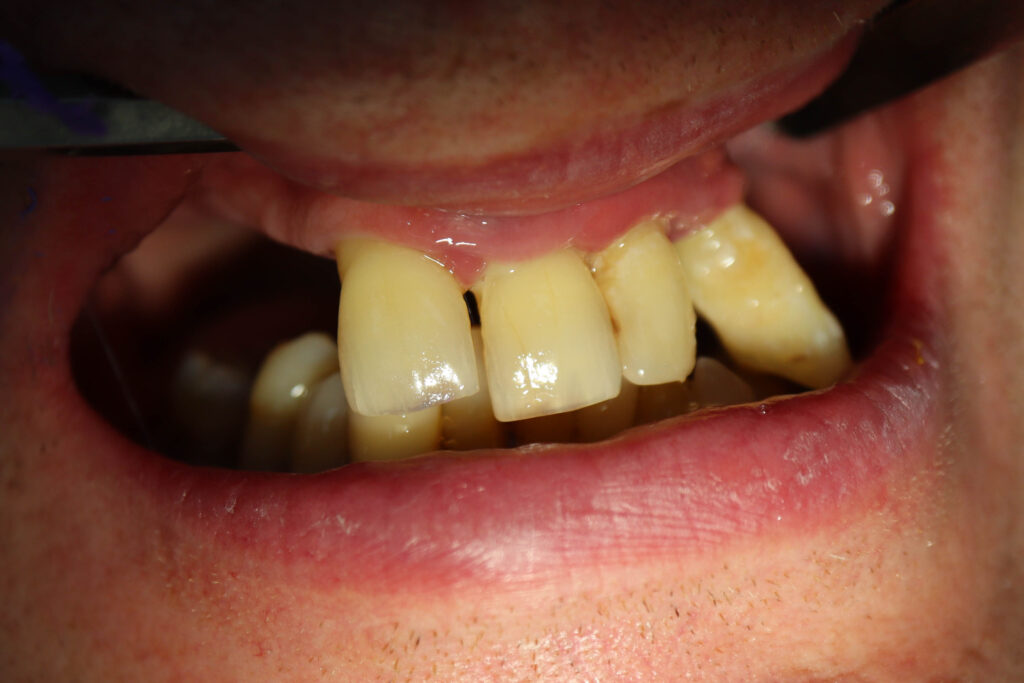

Результат

Результат имплантации